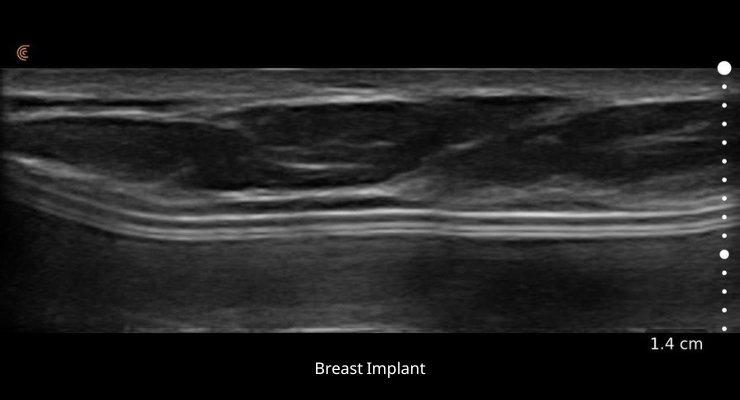

• תמונה חדה וברורה של רקמת השד

• הערכה, זיהוי וטיפול טוב יותר במשתל שד, ריפליניג קפלים ועוד